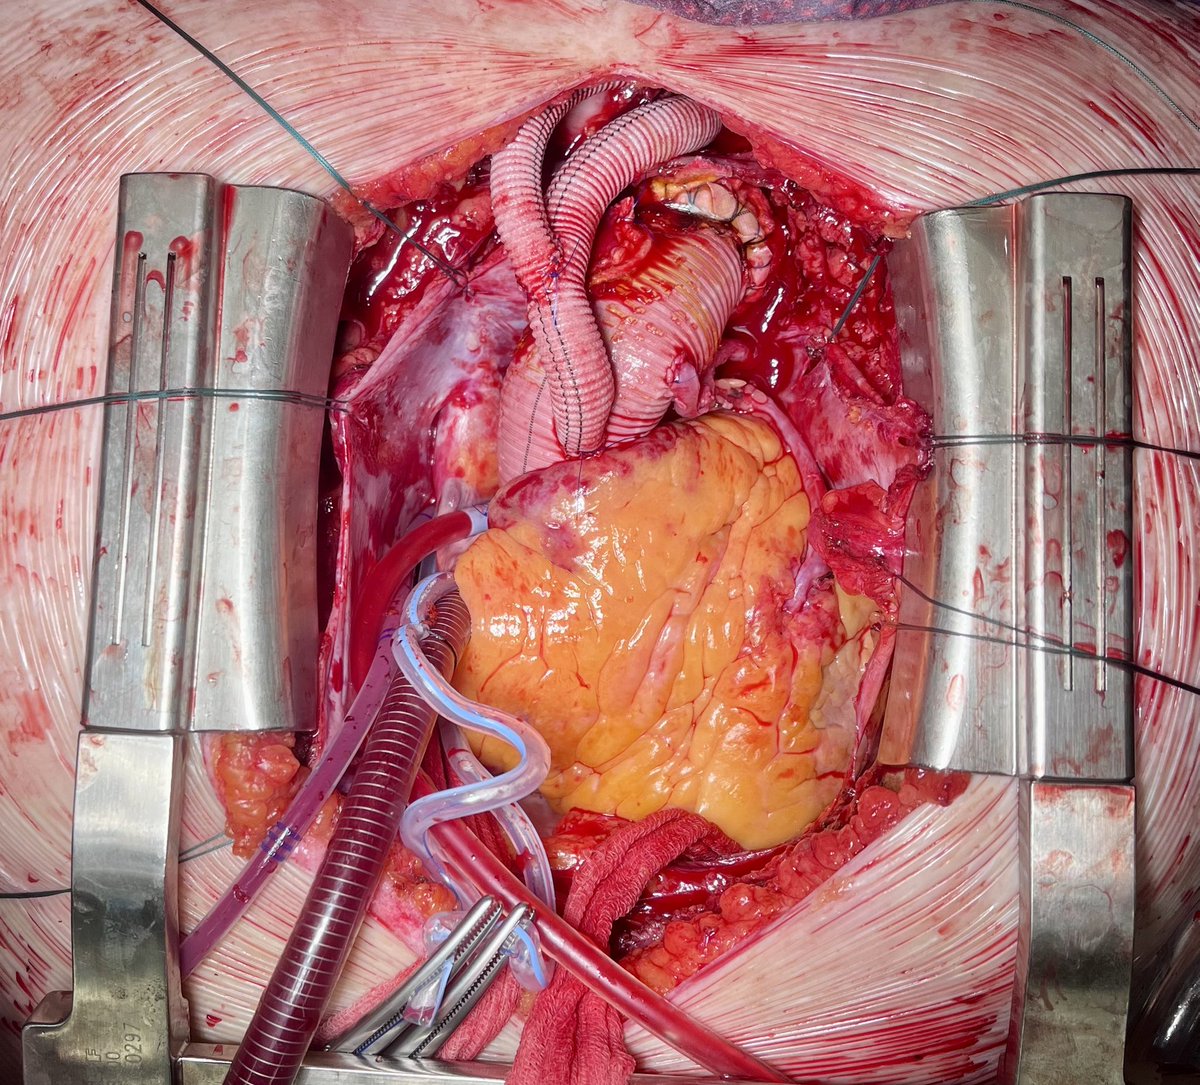

The Future of Aortic Surgery? Typ A Dissection after TEVAR (in another clinic before), treated with Bentall, partial removal of TEVAR, Frozen Elephant 33mm, Debranching of supraaortic vessels, CPB via groin, 55min bilateral antegrade cerebral perfusion. Many thanks to the team!